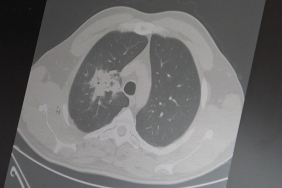

Vücudun taşıyıcı ve hareket sağlayan ana yapısı omurga, yaşam kalitesini doğrudan etkiler. Ancak sanılanın aksine yalnızca ilerleyen yaşla değil; günlük alışkanlıklar, sigara kullanımı ve kilo–kas dengesi gibi faktörlerle de zaman içinde yıpranır. Bu sürecin aslında ‘yaşlanma’ değil, kullanım ile ilişkili bir dejenerasyon olduğunu belirten Beyin ve Sinir Cerrahisi Uzmanı Prof. Dr. Ahmet Hilmi Kaya, “Bel ve boyun ağrılarında hangi durumların doğal sayılabileceğini, hangilerinin değerlendirilmesi gerektiğini ayırt etmek önemli. Her dejenerasyon bulgusu hastalık değildir ancak uzun süren ve ihmal edilen şikâyetler daha ciddi sorunlara zemin hazırlayabilir” dedi.

Omurga yıpranmasını yavaşlatmak için erken tanı ve günlük yükün doğru yönetilmesinin önemine dikkat çeken Beyin ve Sinir Cerrahisi Uzmanı Prof. Dr. Ahmet Hilmi Kaya, “Günlük yaşamda hareketi artırmak, ani ve kontrolsüz zorlanmalardan kaçınmak, kasları kademeli olarak güçlendirmek ve sigara gibi disk yapısını olumsuz etkileyen alışkanlıklardan uzak durmak gerekir. Uzun vadede omurga sağlığını koruyabilen kişilerde ideal kilonun sürdürüldüğü ve aktif bir yaşam tarzı benimsendiğini gözlemliyoruz. Özellikle günlük yaklaşık 7 bin adımın üzerine çıkıldığında, ek bir sağlık sorunu yoksa ağrı ve şikâyetlerin azalacağı bilinmeli” dedi.